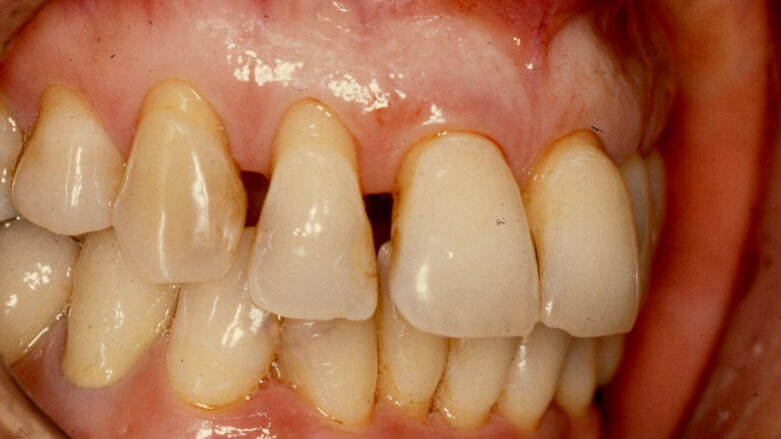

La paziente (che agirà in giudizio) 55 anni, fumatrice con scarso controllo dell’igiene domiciliare, in cura nel 1998 per parodontopatia cronica e compromissione dei quattro incisivi superiori (Figg. 1-5) per dodici anni, viene trattata con terapie chirurgiche e non2. Nel luglio 2010, dopo ben 12 anni di mantenimento di tali denti, si presenta all’osservazione dell’odontoiatra per la rottura dello splintaggio, riferendo di aver subito un accidentale trauma facciale.

Il dentista verifica un aggravamento della mobilità dei quattro incisivi e sollecitato dalla paziente a migliorare l’aspetto estetico, prospetta la sostituzione degli elementi naturali da estrarre, con una protesi fissa su impianti. Al fine di ridurre il rischio di un ulteriore riassorbimento dell’osso alveolare residuo e del collasso dei tessuti molli3-7 della pre-maxilla, prima delle estrazioni degli incisivi, viene prospettata la loro estrusione8, 9.

Tutto ciò viene dettagliatamente spiegato sia verbalmente, sia descritto nel “Consenso informato” che la paziente sottoscrive dopo aver richiesto un secondo consulto presso un altro studio. Il trattamento estrusivo dei due incisivi laterali inizia nel gennaio 2011 (Figg. 7, 8). Al raggiungimento del risultato desiderato (Figg. 9, 10), si attendono 60 giorni di “stabilizzazione” dell’osso alveolare18 (Figg. 11, 12).

Vengono inserite due viti di guarigione e riposizionato il provvisorio, debitamente adattato in corrispondenza dei due incisivi laterali. Alla seduta di controllo a una settimana dall’intervento implantare, la paziente confida, alle assistenti dello studio, di non aver assunto gli antibiotici prescritti né prima né dopo l’inserimento degli impianti e tantomeno di essersi astenuta o limitata dal fumo di sigarette! Alla seconda visita di controllo, dopo 30 giorni, la stessa presenta un pessimo stato di igiene orale e due ascessi vestibolarmente ai due impianti (1.2 e 2.2) (Figg. 17, 18).